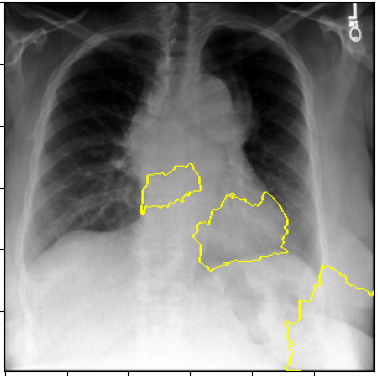

3.3 Interpretability

Post-Hoc Comparisons. We compare our concept-based explanations to post-hoc XAI techniques LIME and SHAP, applied to the baseline InceptionV3 model. The image explanations generated by these techniques disagree with each other and the medical ground truth. We show an example of this observation in Figure 7, where both techniques fail to capture the large mass in the X-ray, and highlight irrelevant regions such as areas outside of the lung as incorrectly important to the classification decision. In contrast, our approach correctly identifies the presence of a mass. More examples are shown in Figure 10.

Refer to caption

(a) Ground Truth

(b) LIME

(c) SHAP

(d) CXR-LLaVA Generated Report

(e) Our Approach

Figure 7: Example of our explanation approach outperforming LIME, SHAP and CXR-LLaVA. Ground truth (a) is a “Large right upper zone mass". LIME (b) and SHAP (c) fail to capture the mass in the X-ray. Most important image regions are bounded by yellow for LIME, and shown in more vibrant green for SHAP. CXR-LLaVA (d) generates a report which wrongly describes the image as non-cancerous. Our approach (e) correctly identifies the presence of a mass.

(a) Ground Truth 1

(b) Ground Truth 2

(c) Ground Truth 3

(d) Ground Truth 4

(e) LIME 1

(f) LIME 2

(g) LIME 3

(h) LIME 4

(i) SHAP 1

(j) SHAP 2

(k) SHAP 3

(l) SHAP 4

Figure 10: Examples of LIME and SHAP explanations failing to capture the medical ground truth of a cancerous chest X-ray, while also generating conflicting explanations. Ground truth (a,b,c,d) is shown as red squares. Most important regions are bounded by yellow for LIME (e,f,g,h) and shown as more vibrant green for SHAP (i,j,k,l).